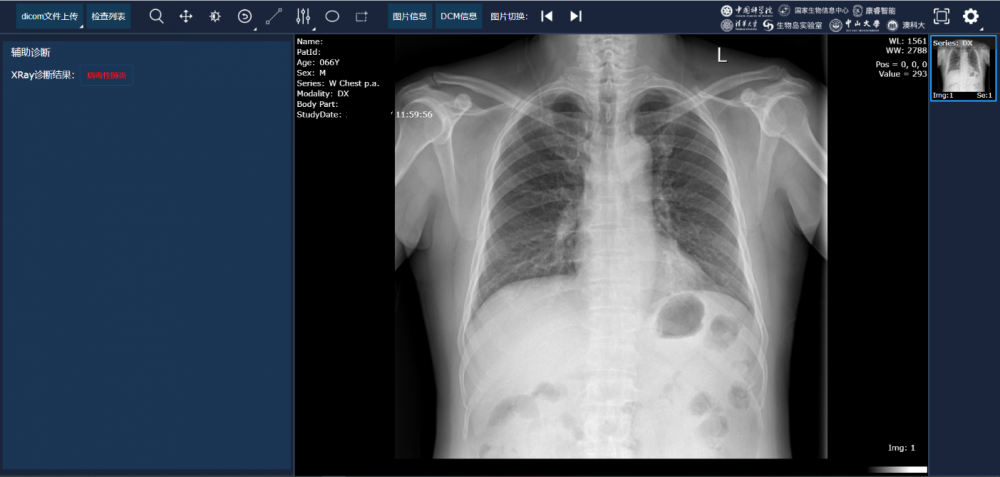

图:基于X-ray胸片的智慧筛查模组,来源:澳门科技大学

据悉,该系统是基于4154名患者总计五十多万份临床影像学大数据,运用深度学习、迁移学习、语义分割等多种人工智能前沿技术,而开发的基于胸部CT和X-ray的新冠肺炎AI辅助诊断系统。不同于传统的端到端的深度学习模型,这套诊断系统融合了两步不同的模型,第一步是基于语义分割的“肺部病灶”模型,其次是基于生成的肺-病灶图谱,将病人的整个CT (大约100~300张切片)作为输入,进一步构建智能诊断模型。这一工作可以避免“黑箱”模型在实际医疗应用中的缺陷,提高AI诊断系统的可解释性和泛化性能,也可以提高诊断的准确度。通过研究来自新冠肺炎患者、普通肺炎患者、以及对照组的CT影像数据,AI学会了对其进行区分。另一点值得关注的是,该研究的AI系统识别了与新冠肺炎病变特性相关的重要临床标志物。连同临床数据,AI系统能够提供准确的临床预后,可以帮助临床医生考虑适当的早期临床治疗并适当地分配资源。

在澳门科技大学官网的一篇报道中,张康教授表示,相比人工阅片,该系统有三大优势。首先是快速、准确地诊断新冠肺炎。据悉,有经验的影像科医生阅完一个患者的胸部CT图像尚需约15至20分钟,而该AI系统则可在20秒内完成诊断过程,且诊断准确率达90%以上,相当于一个省级三甲医院影像学副教授的诊断水准。其次,该系统还具有病情严重程度分级和重症危重症预测功能,可对胸部CT图像每一层面的小结节、磨玻璃影和实变进行自动识别、标注及定量分析,可通过患者的吸氧频率、血氧饱和度、酸碱平衡、肝功能、凝血功能等,综合预测病人发展为重症、危重症的概率和时间,有利医生及时干预,降低患者死亡率。此外,系统能够协助医务人员进行药物效果评估,指导用药,包括对同一位患者用药前后的CT图像对比分析,通过定量计算病人在用药前后的变化,判别药物是否有效,指导临床用药。

论文数据也显示,在自我测试中,这套AI系统诊断新冠肺炎的准确率达到了92.49%(灵敏度94.93%,特异性91.13%)。利用来自不同地区的不同数据集,这套AI诊断系统经受住了真实世界的考验——利用回溯性数据及前瞻研究,该AI系统均可达到90%左右的准确率,即便是使用海外的CT数据,这套系统也达到了84.11%的准确率。这一系列研究结果表明,科学家们开发的这套AI诊断系统无论是采用中国数据,还是国际数据,都能取得较好的表现。